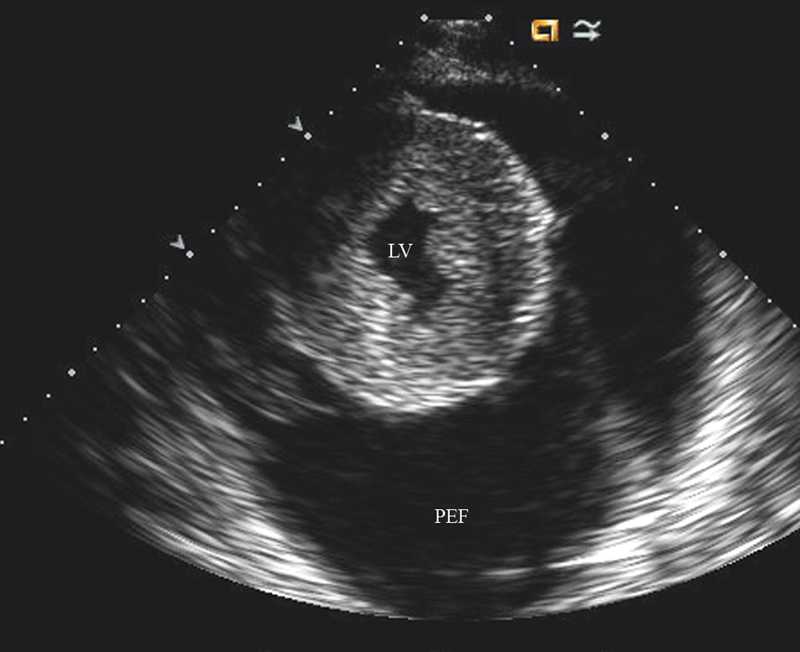

فحوصات تشخيصية لبعض امراض القلب والشرايين التاجية